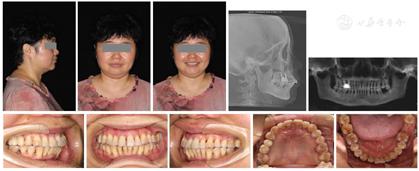

经过矫正前的牙周系统治疗以及22个月的矫正加稳定并联合矫治期间定期的牙周维护治疗,矫治结束后患者上下牙列牙齿排列整齐,建立了正常的覆牙合覆盖,维持了双侧磨牙、尖牙咬合关系,未有咬合干扰点,达到稳定的咬合关系。同时,牙周袋并未加深,11瘘管愈合(图2),全口牙龈颜色正常,牙周组织无活动性炎症出现,另外,患者口内治疗前多颗松动的牙齿,其松动度也有明显的改善,例如治疗前11、22松动Ⅲ°,23松动Ⅱ°,12、36~41松动Ⅰ°。治疗后11、22松动Ⅰ°,其余牙齿稳定无松动现象。X线表现(图9)治疗后牙槽骨吸收停止且23~26近远中,36远中以及27近中等部位均有少量牙槽骨再生,骨白线连续性亦有增加,下前牙区牙槽骨高度有少量增加。关节矢状面、冠状面保持稳定,FloridaProbe牙周检查最终探诊深度普遍降至1~3 mm。X线头影测量前后对比以及重叠图可见上前牙内收较明显,下切牙压低有效,侧貌突度明显改善(图10,图11,图12,图13,图14)。

2.在正畸矫治过程中,矫治力的把控是至关重要的。轻力少幅度矫治利于维护牙周组织健康,并在矫治过程中选择性调牙合,消除早接触,对牙周组织稳定的维护也是不容忽视的。本病例在牙周治疗基础上采用的固定松动牙、微小牙齿移动等是目前牙周炎辅助治疗的有效手段[7],通过正畸治疗,本病例达到了非常满意的效果,矫治后间隙关闭,上下前牙突度改善,患者矫正前U1-SN减小了8.2°,U1-NPo距减小了近3°,上下唇的位置关系最终达到位于E线上,明显改善了患者的侧貌突度。牙齿移动结束后,本病例采用上下颌舌侧丝固定保持及负压压膜活动保持正畸效果。